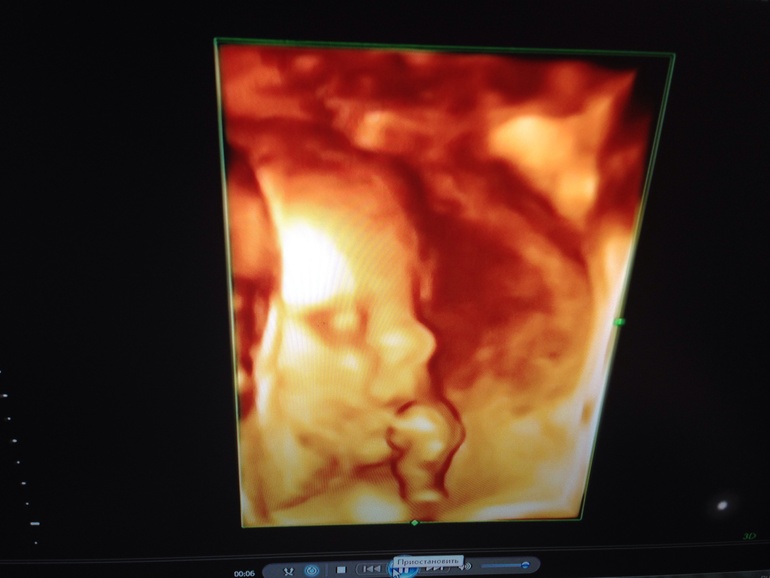

Ну и наш пузик)

Шевеления активные, икота у малыша появилась)

И сидит наш пацан на попе (в прошлый раз лежал поперек), разговариваю с ним, объясняю, что надо б перевернуться, но время еще есть, думаю сам знает когда и как повернуться) точнее надеюсь)) такие вот дела) чувствую, скоро понесет меня за покупками вещичек мальчуковых))) а пока наслаждаюсь своим положением)